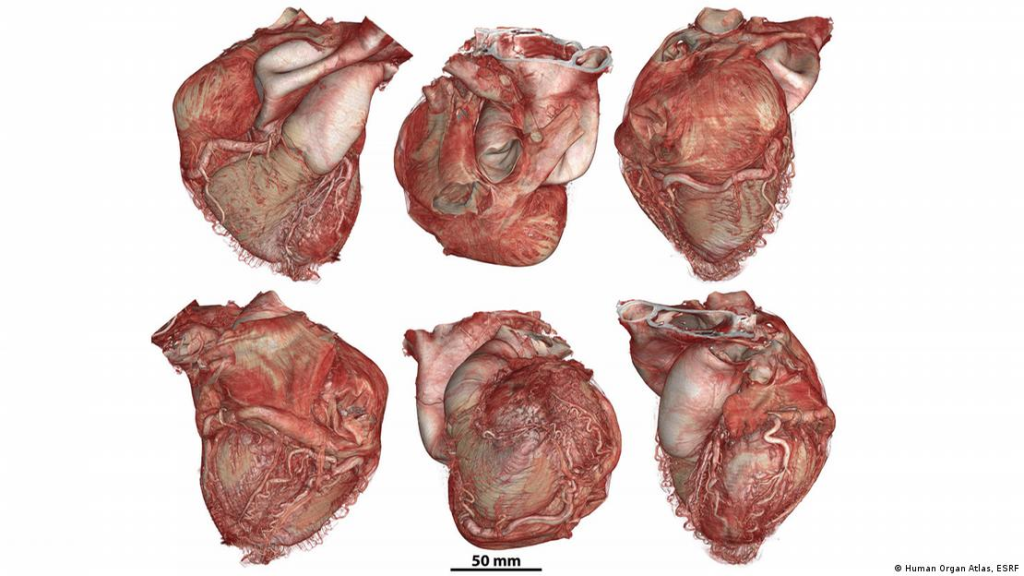

Entre los logros destacados del proyecto se encuentra el escaneo completo en 3D de un colon humano con una resolución cercana a la escala celular, un hito sin precedentes en la historia de la imagen biomédica. Asimismo, el atlas ha capturado órganos como el corazón desde múltiples perspectivas, revelando su organización interna con una precisión inédita, lo que abre nuevas vías para la comprensión de su funcionamiento y de las patologías que lo afectan.

La base de datos incluye actualmente 65 órganos correspondientes a 13 tipos diferentes y reúne 321 conjuntos de datos tridimensionales completos obtenidos de 32 donantes. Entre los órganos disponibles se encuentran cerebro, corazón, pulmones, riñones, hígado, colon, bazo, placenta, útero, próstata, ojo y testículos. El portal ofrece visualización interactiva, descarga de datos en distintas resoluciones, tutoriales y herramientas de software, con actualizaciones periódicas que incorporan nuevos registros.